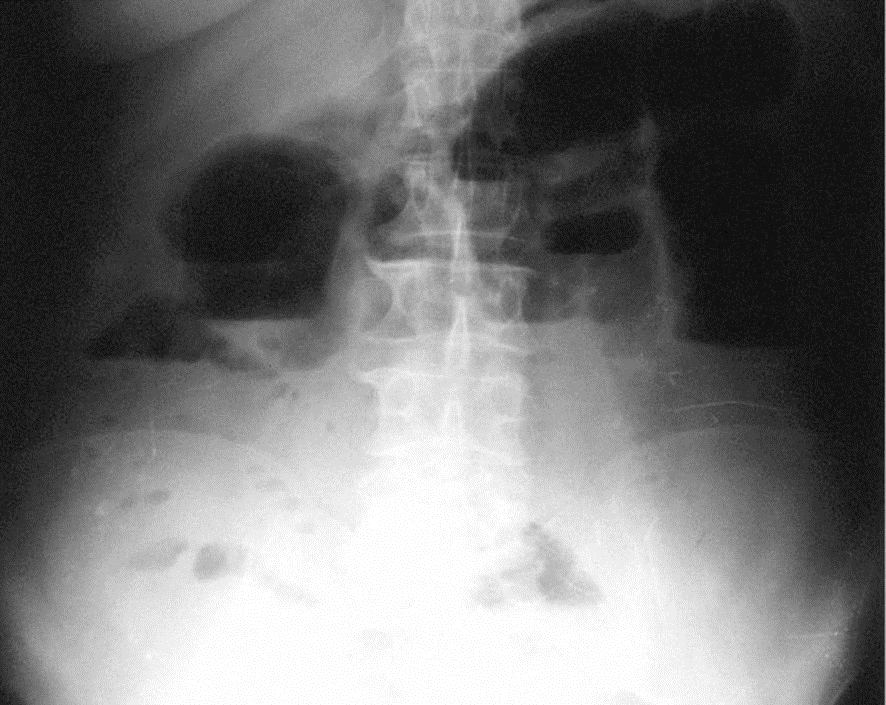

La radiografía simple de abdomen en decúbito supino y/o en bipedestación (o en decúbito lateral izquierdo con rayo horizontal en enfermos que no pueden mantenerse de pie) muestra distensión generalizada del tracto digestivo, con niveles de líquido.